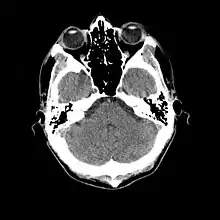

L'examen complémentaire essentiel à l'identification d'une méningite est l'analyse du liquide cérébrospinal obtenu par ponction lombaire[27]. Toutefois une telle ponction est contre-indiquée en cas de masse cérébrale (tumeur, abcès) ou d'hypertension intracrânienne, pouvant entraîner un engagement cérébral. En cas de situation à risque (traumatisme crânien, déficit immunitaire, signe neurologique focal, signe clinique d'hypertension intracrânienne), une imagerie cérébrale préalable est recommandée, avec un scanner ou une IRM[10],[26],[28]. C'est une situation concernant potentiellement environ 45 % des cas adultes[9]. Lorsqu'une imagerie est effectuée avant la ponction ou que celle-ci se montre difficile à réaliser, il est suggéré d'administrer un traitement antibiotique immédiatement afin de ne pas retarder le délai de mise en route du traitement[10], surtout si une telle attente est prévue pour dépasser 30 minutes[26],[28]. Souvent, lorsque l'imagerie n'est pas faite initialement, elle est faite plus tard dans les cas où il existe une complication[3].